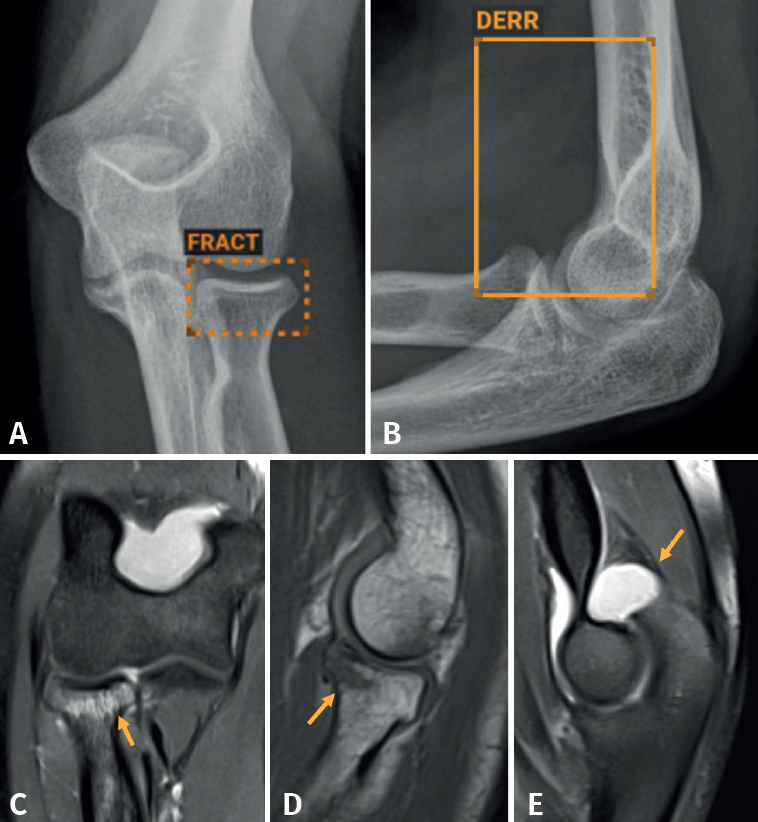

Aunque no hemos realizado un estudio de sensibilidad y especificidad por la complejidad que entraña en la práctica asistencial, consideramos que los resultados son satisfactorios, en línea con lo publicado en la literatura científica. Destacamos la eficacia del algoritmo en la detección de pequeñas fracturas arrancamiento (Figura 3), fracturas de radio distal y proximal (Figura 4), y fracturas múltiples (Figura 5).